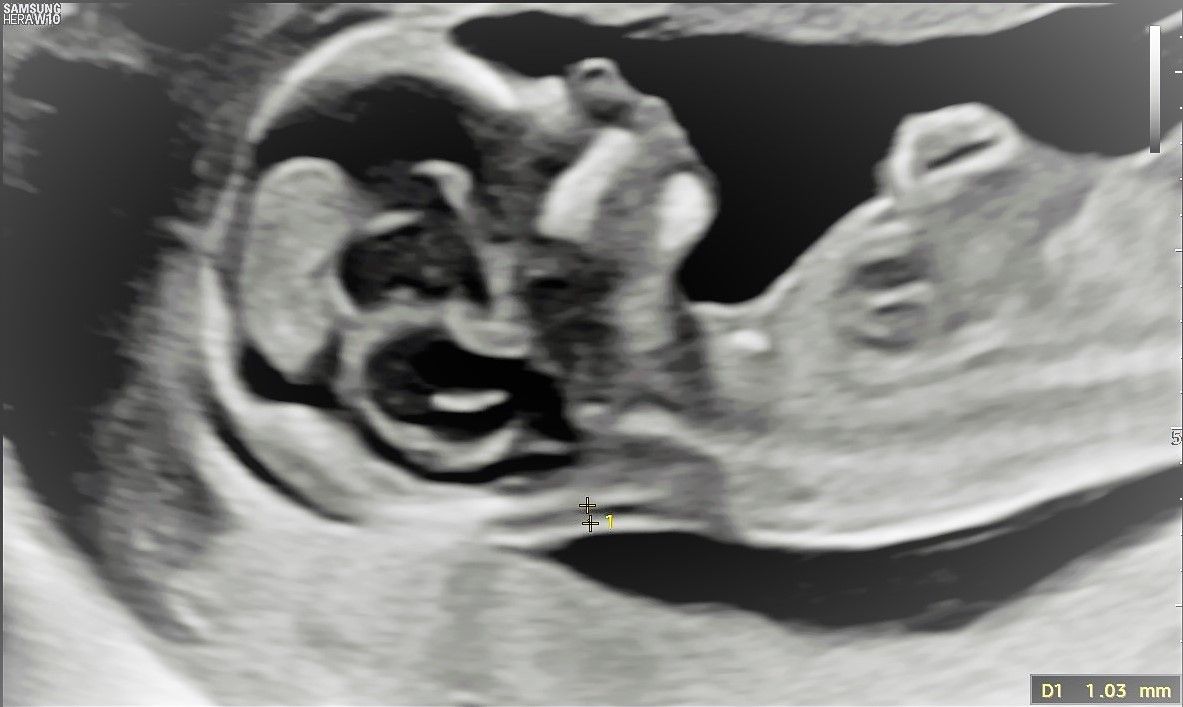

Das Ersttrimester-Screening wird zwischen der 12. und 14. Schwangerschaftswoche durchgeführt. In das Ergebnis der Untersuchung geht die Kombination von verschiedenen Meßwerten ein (s.u.).

Bei der qualifizierten Ultraschalluntersuchung wird bei dem ungeborenen Kind ein Bereich des Nackens gemessen, der als Nackentransparenz (NT) bezeichnet wird,, desweiteren wird die Scheitel-Steiß-Länge des Feten gemessen. Im Blut der Schwangeren werden die Konzentrationen zweier Substanzen, das PAPP-A und das freie Beta-hCG, gemessen. PAPP-A und Beta-hCG sind Eiweißsubstanzen, die in einer bestimmten Menge üblicherweise nur während einer Schwangerschaft vorhanden sind.